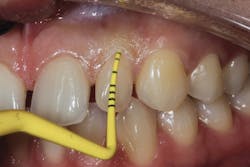

With these indications in mind, does every extraction socket need to be grafted? The answer is no. A good decision matrix is based on “A Simplified Socket Classification and Repair Technique” by Elian et al.9

Classification when existing tooth is still present

Type 1 socket—Buccal plate present and soft tissue present

• Type 1 socket (figure 19)—Thick biotype, posterior tooth, and buccal plate present: no graft needed